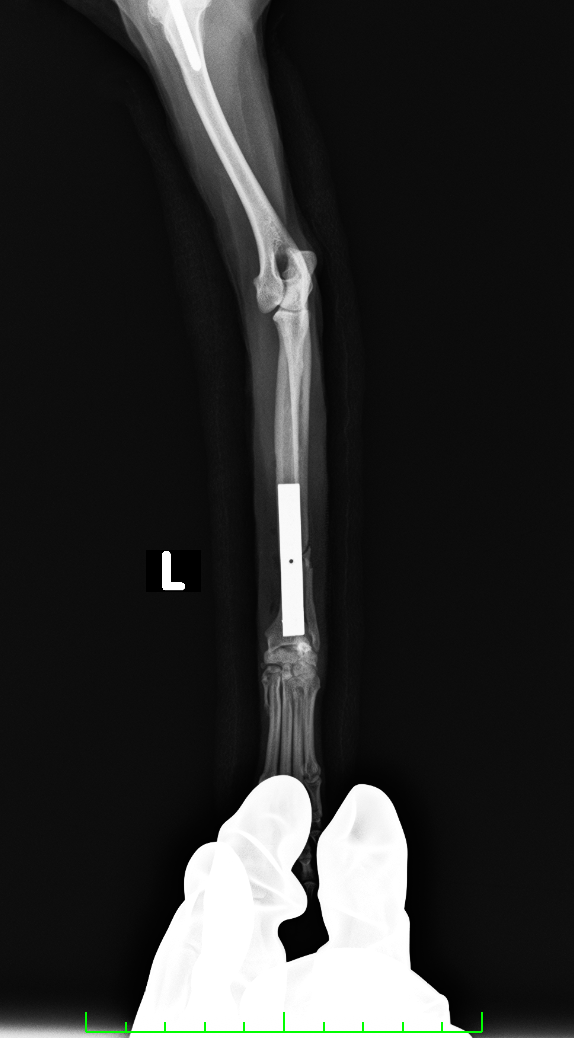

右上腕骨頭において、2.0のドリルビットを用いて皮質骨を貫通し、キュレットで海面骨を採取した

2.0のカッタブルプレートを使用し、コンベンショナルスクリューを用いた

after